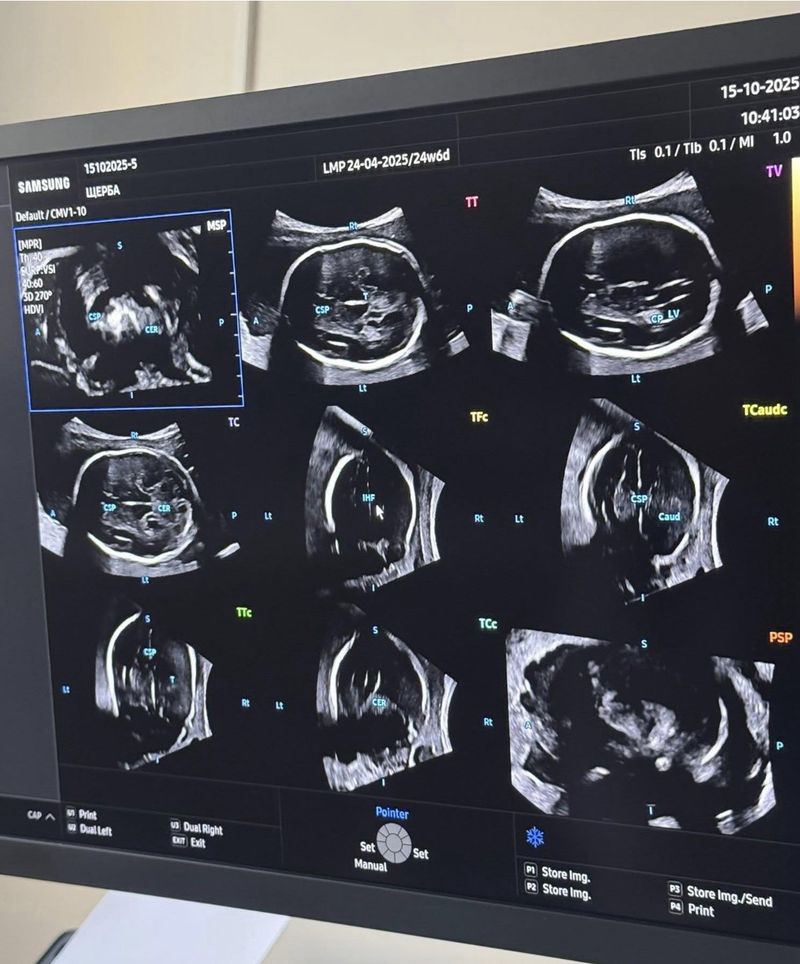

“HERA Z20 автоматично розпізнає анатомічні структури, проводить точні вимірювання та формує об’ємні зображення в реальному часі. 5D Ultra Live, Crystal Architecture™ та AI ScanAssist забезпечують неймовірну реалістичність — батьки можуть побачити обличчя й рухи своєї дитини ще до народження. Для лікарів це — можливість виявляти найменші відхилення розвитку на ранніх етапах і приймати рішення, що рятують життя”, – йдеться у повідомленні.

Апарат відкриває новий стандарт пренатальної діагностики, спостереження за вагітністю та охорони репродуктивного здоров’я жінок.